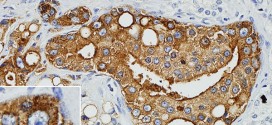

Los tumores malignos de próstata. Publicado en: binipatia.com Escrito por: Salvador Gregori y Abby Schaffner Etiquetas: sustancias súper nutritivas, tratamiento natural, reishi, vitamina D3 Resumiendo: La próstata es un órgano del sistema reproductor del varón. Es una glándula, con forma de castaña, colocada debajo de la vejiga y por delante del recto. La uretra (conducto por donde sale la orina) atraviesa la …

Leer MásCARCINOSARCOMA DE PRÓSTATA

El carcinosarcoma de próstata. Publicado en: binipatia.com Escrito por: Salvador Gregori Escrivá y IJosh Bush Etiquetas: sustancias súper nutritivas, promover la salud verdadera, arsenal terapéutico alternativo Se trata del tumor maligno más frecuente en los seres humanos. En varones. Durante los primeros años de vida de una persona, las células normales se dividen más rápidamente para permitir el crecimiento. El cuerpo está …